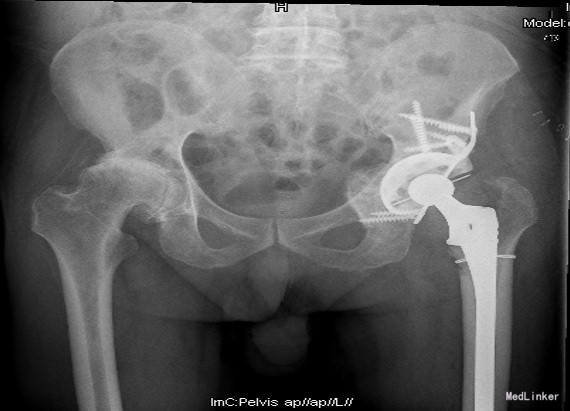

查体:左腹股沟区可见瘢痕及色素沉着,左腹股沟区可触及质硬包块,触之胀痛,局部皮温正常,左下肢内侧皮肤麻木。左髋外展10°,内收10°,屈曲80°,伸0°,内旋0°,外旋5°,右髋外展20°,内收15°,屈90°,伸0°,内旋10°,外旋10°,双髋内、外旋活动诱发疼痛;双下肢基本等长,双侧4字试验(+)。 辅助检查:双髋内、外旋活动诱发疼痛;双下肢基本等长,双侧4字试验(+)。X线片:左髋THA后假体向上移位,右侧股骨形态失常,关节间隙变窄

诊断:1.左侧THA术后假体松动、聚乙烯内衬磨损、炎性假瘤形成 2.左侧THA术后髋臼及股骨近端骨溶解 3.左侧THA术后髋臼及股骨近端骨缺损(髋臼AAOS III型 股骨Paprosky II型) 4.右髋重度骨关节炎 5.高血压 (2期 高危) 治疗:完善检查,调整患者全身条件后在全麻下行左侧全髋关节假体取出+炎性假瘤切除+异体骨植骨+髋臼重建+人工全髋关节翻修术,术中发现:左髋关节囊后外侧炎性假瘤形成,与关节腔相通,内有大量咖啡色混浊液体,髋臼及股骨近端骨溶解导致骨缺损,以髋臼前壁及下壁和股骨近端严重,小转子消失,关节腔周围大量炎性坏死组织。髋臼假体松动。术中安放左侧Zimmer64mmCage,并用8枚不同长度螺钉固定可靠,Cage内放骨水泥后安放外径59mm,内径28mm聚乙烯内衬并调整前倾及外展角度合适,股骨侧安放12#加长股骨柄,28mm直径、+1.5颈长陶瓷股骨头。